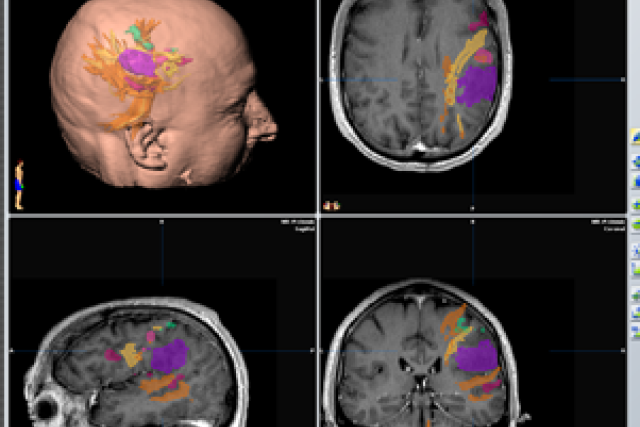

Functional MRI scanning fused to intra-operative neuro-navigation technology allows doctors to create a personalized virtual 3D model of a patient’s tumor (purple) relative to normal functional areas of the brain that control motor function (green) and language function (yellow/orange). This allows neurosurgeons to visualize the areas of the brain to avoid before going into surgery, so they can more safely take out tumors near areas that may previously have been considered inoperable. (Image courtesy of Dr. Linda Liau)

That’s where functional magnetic resonance imaging (fMRI), which allows brain mapping before surgery, comes in. “We’re one of the leading centers that does functional MRI scanning in conjunction with intra-operative brain mapping,” Dr. Liau said. “We’re able to use cutting-edge imaging technology and brain stimulation in real time to better inform our surgeries.”

In Widener’s case, the tumor was in the frontal and parietal lobes on the left side of his brain, in between his primary motor-sensory areas and encroaching upon language areas, which made the operation more difficult.

During a pre-surgery scan, Widener was asked to perform specific tasks that then caused the corresponding areas in his brain to light up on the brain scan. That helped pinpoint which areas to avoid during surgery.

Widener’s scan was then used to create a three-dimensional model of his brain. “It takes quite a bit of post-processing to really interpret those functional MRI scans to use them for surgical localization,” Dr. Liau said.

“It’s a very informative, interactive map – we’re able to map out not just the neurons, but also all of the fiber tracks connected to those neurons,” she said. Even so, she noted, “during surgery, we still have to stimulate the neurons in the brain to determine if they are working while we take out the tumor.”

That meant using functional mapping fused to intra-operative navigation during the surgery to precisely locate areas of the brain to stimulate and measure the response using electrodes. “For example, if I stimulate a specific area in the brain and that causes twitching in the face, arms, or legs on the opposite side, then I know that’s a primary motor area and to avoid it,” Dr. Liau said.